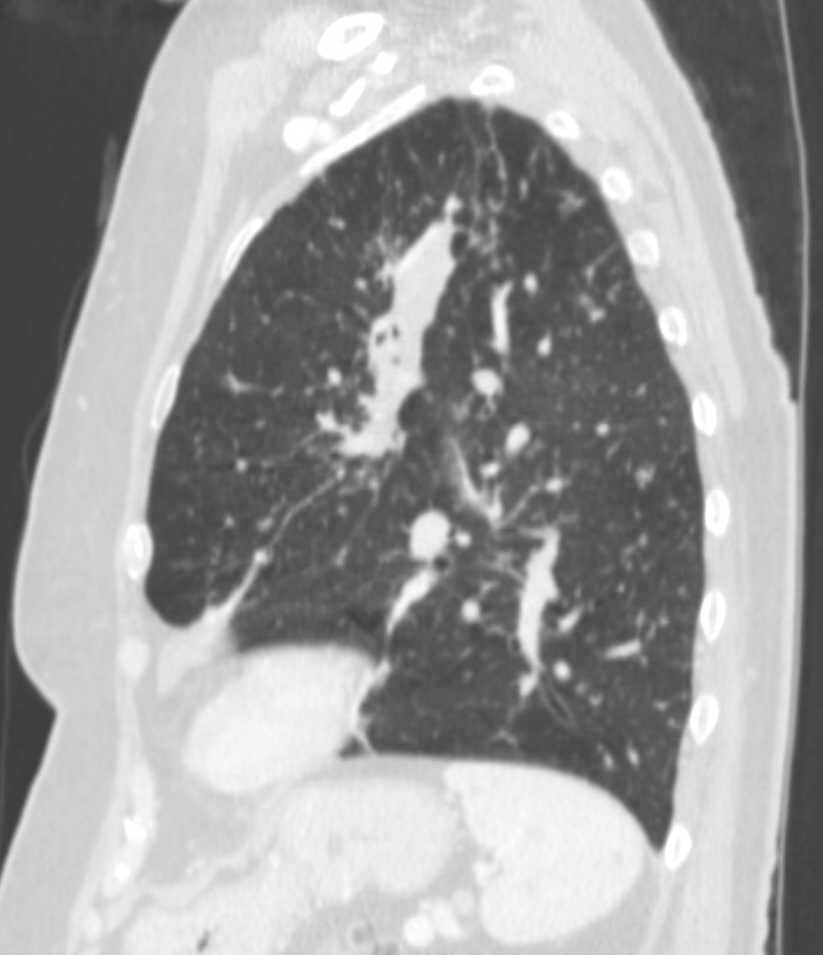

4: Miliary pattern: sarcoidosis, CT, lung window. Axial image and sagittal reformat.

A 67 year old female suffering from COPD. Bilateral rough branching interstitial widening and patchy, miliary nodules with perihilar dominance along the bronchovascular fibres and the fissures.